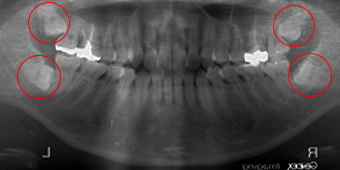

左側を見て頂きたいのですが 上下とも水平で下顎は埋伏位置も深く根っこも二つに分かれ開いており、上顎も手前の歯に当たりめり込んでいる複雑な症例です。上下で25分位かかりました。

左右上顎を見て頂きたいのですが手前の歯に当たり複雑な様相を見せてますが、左右とも10分程度で抜けた症例です。しかし右下はかなり深く又下歯槽神経に近い為慎重にも慎重を重ね20分ほど時間をかけました。左下は埋伏位置も深く下向きな為少し難症例で15分程度です。